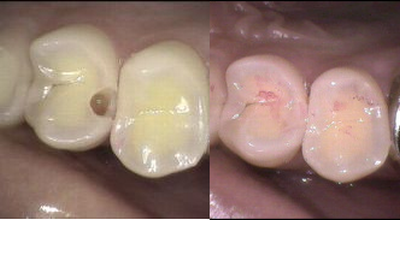

虫歯治療

当クリニックでは、MI(MinimalIntervention)治療を行っています。

MI治療というのは、極力歯を削らずに、今ある歯をできる限り残すという考えの治療法です。

歯を必要最小限しか削らないMI治療は、歯

を残す観点からも、長期的に観て非常に有意義です。

この方法では、主に光CR(光で重合するコンポジットレジン)を使用します。